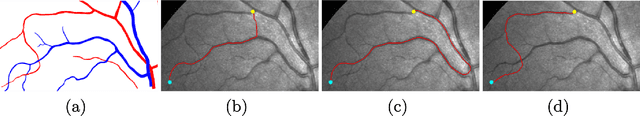

Tubular structure tracking is an important and difficult problem in the fields of computer vision and medical image analysis. The minimal path models have exhibited its power in tracing tubular structures, by which a centerline can be naturally treated as a minimal path with a suitable geodesic metric. However, existing minimal path-based tubular structure tracing models still suffer from difficulty like the shortcuts and short branches combination problems, especially when dealing with the images with a complicated background. We introduce a new minima path-based model for minimally interactive tubular structure centerline extraction in conjunction with a perceptual grouping scheme. We take into account the prescribed tubular trajectories and the relevant curvature-penalized geodesic distances for minimal paths extraction in a graph-based optimization way. Experimental results on both synthetic and real images prove that the proposed model indeed obtains outperformance comparing to state-of-the-art minimal path-based tubular structure tracing algorithms.